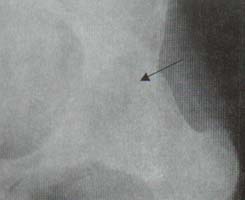

Las articulaciones periféricas más comúnmente comprometidas son: cadera, hombro, rodilla y metatarsofalángicas. Las caderas se comprometen en el 50% de los pacientes y el compromiso se caracteriza por disminución del espacio articular, migración axial de la cabeza femoral, y osteofitos en forma de collar en la unión de la cabeza con el cuello (Figuras 8 y 9).

Figura 8. Cadera. Disminución del espacio articular,

migración axial de la cabeza femoral, esclerosis subcondral acetabular y

osteofitos alrededor de la cabeza femoral (Flecha).

Figura 9. Cadera. Anquilosis completa con formación de

puentes óseos entre la cabeza y el iliaco (Flecha).